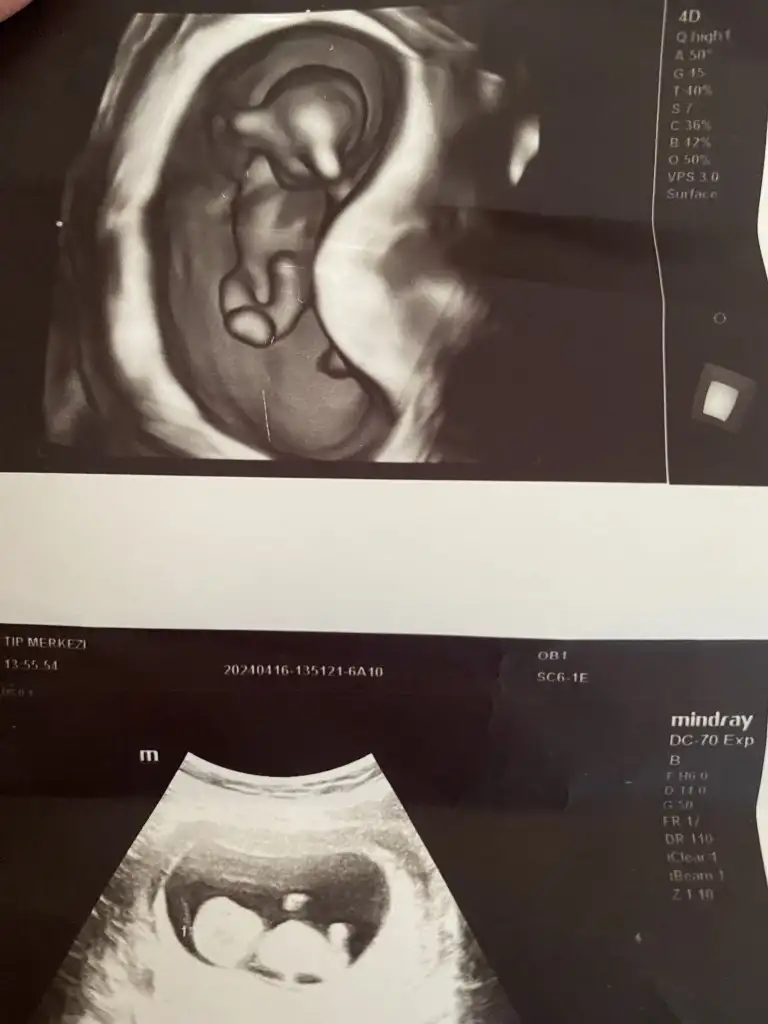

Bu da benimki 14+4 olduk bir bakın kızlar sizce ne doktor belli değil dedi henüz. Bir başka doktor da erkek gibi duruyor dedi bilemedik valaKızlar bebişlerinizin ultrason resimlerini ve cinsiyetini kaçıncı haftada olduklarını yazında kendi ultrason resimlerimizle kıyaslayıp fikirde bulunalım. Nub teorisi, kafa şekli, kemik yapısından cinsiyet teorileri tutuyor mu bakalım bir

Evet canım hala erkek geliyo bana sırtını dönmüş ama başka var mı düzgünEki Görüntüle 3393072

Merhaba canım sen erkek demiştin bugün doktora gittim oda erkeğe benzetti ama bilemiyorum ya tam net söylemiyor bu da yeni çekilen ultrason fotoğrafı ne diyorsun hala erkek mi